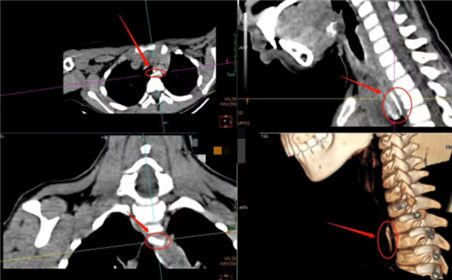

5岁女孩被猪骨卡喉半小时。

43岁大叔4小时前被鸡骨卡咽喉,且刺穿食管,引起食管周围及上纵膈内较多游离气体。